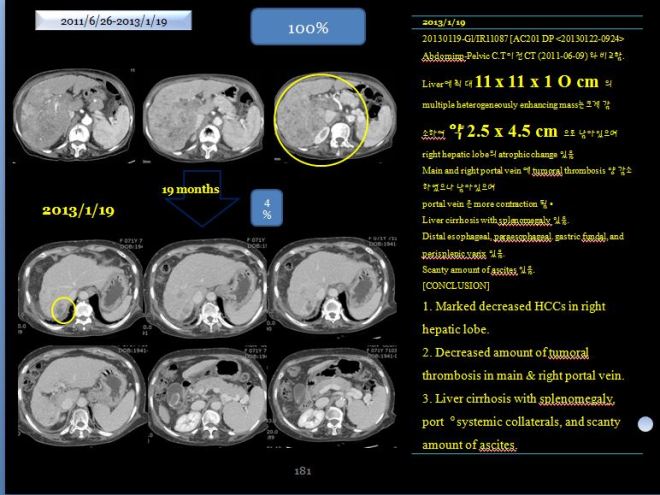

사진에서 보듯이 간은 위축이 되었지만 커다란 종양은 거의 없어져서 일부분만 남아 있다. 당시 의무기록을 보면,

- 20130119-Gl/IR11087 [AC201 DP

- Abdominp-Pelvic C.T 이전 CT (2011-06-09)와 비교함.

- Liver에 최대 11 x 11 x 10cm의 multiple heterogeneously enhancing mass는 크게 감소하여 약 2.5 x 4.5 cm 으로 남아 있으며 right hepatic lobe의 atrophic change 있음.

- Main and right portal vein에 tumoral thrombosis 양 감소하였으나 남아 있으며

- portal vein은 more contraction 됨.

- Liver cirrhosis with splenomegaly 있음.

- Distal esophageal, paraesophageal, gastric fundal, and perisplenic varix 있음.

- Scanty amount of ascites 있음.

- [CONCLUSION]

- Marked decreased HCCs in right hepatic lobe

- Decreased amount of tumoral thrombosis in main & right portal vein

- Liver cirrhosis with splenomegaly, port。systemic collaterals, and scanty

- amount of ascites

“2011년 년 6월 9일과 2013년 1월 19일 CT 를 비교함. 간에 있던 최대 장경 11x11x10cm의 균일하지 않케 조영되는 암은 크게 감소하여서 2.5x 4.5로 줄어들었다. 우측간은 위축되어 있고, main과 우측의 portal vein의 종양에 의한 thrombosis 양이 줄어들었으나 남아 있고, portal vein (문맥)은 더욱 수축되어 있다. 간경화와 비장종대도 있다. 식도와 위장 부근의 비장 옆의 정맥류가 보이며 약간의 복수가 있다.”

18 개월만에 간의 종양이 거의 체적대비하여서 4% 정도로 줄어들었고 2014 년도 3월에 통합의학대회에서 본인이 강의하기 전에 환자에게 CT 를 찍어볼 것을 권유하였다. 이분은 광주분이라 거의 내원을 하지 않고 전화상담과 약물만 꾸준히 지어서 복용하였는데 만 3년이 넘은 2014년 봄에는 더욱더 종양이 줄어들었지만 부분적으로 재발소견을 보였다.